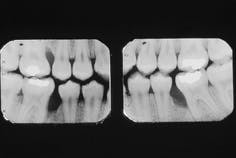

Bitewing radiographs for the 14-year-old patient can be seen in figure 2. Severe vertical loss of alveolar bone on the mesial aspects of the mandibular right and left first molars and the maxillary right first molar is evident. Bone loss localized to the first molars and incisors is characteristic of this disease entity. The image seen on the radiographs is typical of localized juvenile periodontitis.

Note that, although three of the first molars are affected, no significant bone loss can be seen on the adjacent posterior dentition. The maxillary left first molar is not affected in this case. Previous clinical investigators of localized juvenile periodontitis have reported that bone loss does not always occur on all four first molars. In addition, the incisors are also not always affected.

Figure 2: Bitewing radiographs of the patient reveal severe bone loss on the mesial aspects of teeth #3, 19, and 30.